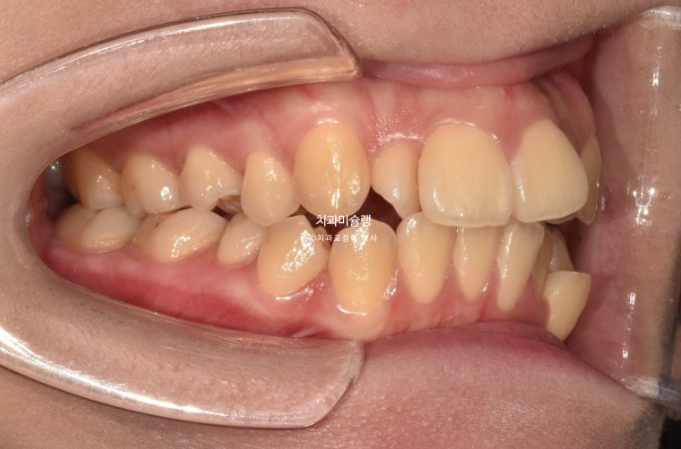

23년 10월 교정치료를 이해 온 30대 환자분입니다.

약 2mm 정도의 중심선 불일치 그리고 덧니가 보입니다.

개방교합도 있고

30년간 공간이 없어서 미처 내려오지 못한 작은어금니도 있습니다.

덧니가 워낙 심해 작은어금니 4개 발치가 불가피한 상황입니다.